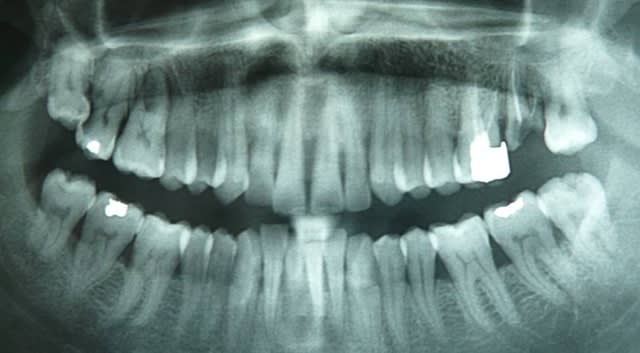

Quelle aproche auriez-vous quant au "traitement" de 18/17 ?

Privilégier la conservation de 18 ou de 17 ?

Tu devrais peut être faire une rétro, mais la 7 est probablement irrécupérable. Malheureusement tu ne feras sans doute rien non plus de ta 8.

Amha, vire la 8, confirme la disposition de ta carie et vire la 7.

Ah bon, on ne s'embête plus à soigner les dents maintenant ? La 8 OK, elle ne peut pas être utilisée. La 7 cela me paraît tout à fait récupérable moyennant quelques efforts (pulpec + obt coronnaire + couronne).

Je demande à voir la gueule de la furcation entre la DV et la P !

Si c'est récupérable tant mieux, et dans ce cas rien de mieux que la vision directe après extraction de la 8 !

Si la carie ne descendait pas autant en distal de 17, la réponse serait beaucoup plus facile, c'est sûr. Pour pimenter le jeu, ci dessous une vue complète ; pas très visible, le plancher de la 27 est carié.

je pense que la 7 est irrecuperable, dans ce genre de cas, je mes souviens des paroles d'un de mes prof d'endo qui disait que la résorption n'était pas que distale mais circonferentielle à la face distale, en forme de croissant.

ceci dit si tu veux garder la 8, ça doit pas être évident de dégager la sept sans y toucher.

moi je virai la 7 , curetage de 6 et 8 puis os de substitution dans l'alvéole.

laisser la 7 avec son dévellopement paro met en danger 6 et 8.

une rétro de la 6 ?

mais honntement pas d'espoir pour la 7 ni pour la 6, la 8 est une fantaisie,mais aucun interet de la garder.

effectivement, il manque quelques données au problème, mais à vue de nez, je ferai ext de 18, soin +/- TR, +/- couronne sur 17, le tout dans le cadre d'un traitement paro, qui semble ici necessaire...